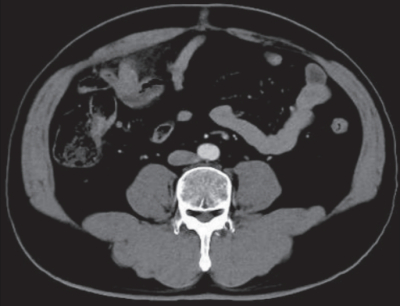

血液所見:赤血球 486 万、Hb 15.0 g/dL、Ht 44 %、白血球 18,000(好中球82 %、好酸球 1 %、好塩基球 1 %、単球 6 %、リンパ球 10 %)、血小板 26 万、PTINR 0.9(基準 0.9~1.1)。 血液生化学所見: 総蛋白 8.1 g/dL、 アルブミン5.1 g/dL、総ビリルビン 1.2 mg/dL、AST 23 U/L、ALT 30 U/L、LD 166 U/L(基準 120~245)、ALP 39 U/L(基準 38~113)、γ-GT 25 U/L(基準 8 ~50)、アミラーゼ 44 U/L(基準 37~160)、CK 64 U/L(基準 30~140)、尿素窒素 17 mg/dL、クレアチニン 1.2mg/dL、 尿酸 6.4 mg/dL、 血糖 109 mg/dL、Na 140 mEq/L、K 3.9 mEq/L、Cl 101 mEq/L、Ca 9.8 mg/dL。CRP 19 mg/dL。 腹部造影 CTを別に示す。

この患者の治療法で適切なのはどれか。

a. 緊急手術